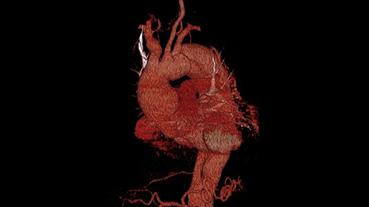

In 2025, cardiologists and cardiac surgeons at NewYork-Presbyterian led breakthroughs that impacted a range of diseases and conditions from advanced heart failure to pediatric valve disease. Physicians and researchers from Columbia and Weill Cornell Medicine pioneered the use of artificial intelligence to identify structural heart disease, launched a mobile app to expand access to heart failure education, performed one of the first split-root domino partial heart transplants, and more. Our experts remained at the forefront of innovative, multidisciplinary care, delivering comprehensive treatment for the most complex cardiac diseases.

Our world-renowned Columbia and Weill Cornell Medicine physicians and surgeons in our comprehensive cardiology, heart surgery, and vascular programs spearhead groundbreaking clinical and scientific research and provide the most innovative treatments to optimize patient outcomes for all stages of disease complexity. Our clinicians are experts in minimally invasive approaches and novel therapeutics for all types of heart disease and work across disciplines to provide compassionate care to all patients.